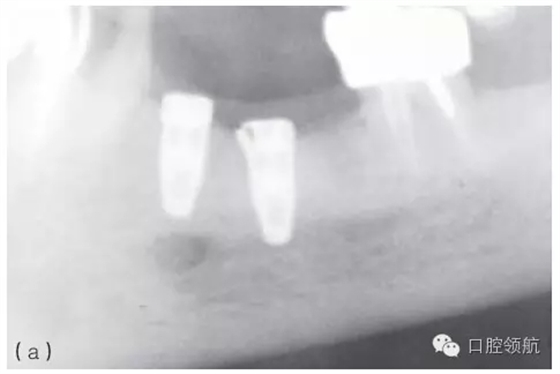

因種植體裝置界面的扭矩可能會(huì)使平臺(tái)連接出現(xiàn)潛在的變形,故應(yīng)注意使該扭矩最小化。Ⅳ類骨植入種植體時(shí)要優(yōu)先在骨上敲打擠壓而不是依靠種植體來(lái)擠壓骨洞。許多廠家會(huì)提醒不要超過(guò)手術(shù)操作時(shí)推薦的扭矩,以減小折斷的可能性(圖5.3a~c)。

圖5.3 (a)Ⅰ類骨中的種植體內(nèi)連接和界面破損的影像學(xué)表現(xiàn)。(b)取出種植體,發(fā)現(xiàn)沿著種植體平臺(tái)的損壞。(c)在重新放置的種植體上行聯(lián)冠修復(fù)完成2年后的影像學(xué)表現(xiàn)。